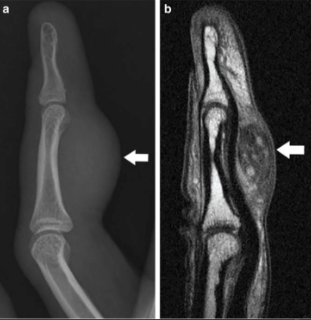

Histologically, these tumors show a positive staining pattern for vimentin, CD68, and 5MA, while being negative for S100, keratin, CD45, Factor VIII, and desmin. Preoperative imaging, typically with MRI, is essential for evaluating the extent of the tumor and its borders, as these tumors appear hyperintense on fluid-sensitive imaging and enhance with gadolinium contrast. This is crucial since postoperative tissue changes can mimic tumor presence.

Ongoing follow-up includes annual clinical evaluations of the excision site, lymph node assessment, and chest X-rays. In this case, our patient was referred to hand surgery for further excision and histologic evaluation of any residual tumor.